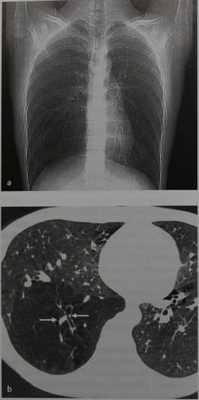

Атрезия правого нижнедолевого бронха у мужчины 20 лет.

А- Локальная эмфизема нижней доли правого легкого была выявлена случайно на обзорной рентгенограмме грудной клетки.

b - Данные КТ коррелируют с картиной, выявленной при рентгенологическом исследовании: выраженная воздушность и повышенная прозрачность в сочетании с обедненным сосудистым рисунком, уменьшение калибра сосудов и более прямолинейный их ход; в центральной части виден расширенный бронх, оканчивающийся слепым карманом без признаков задержки слизи в нем <стрелки).